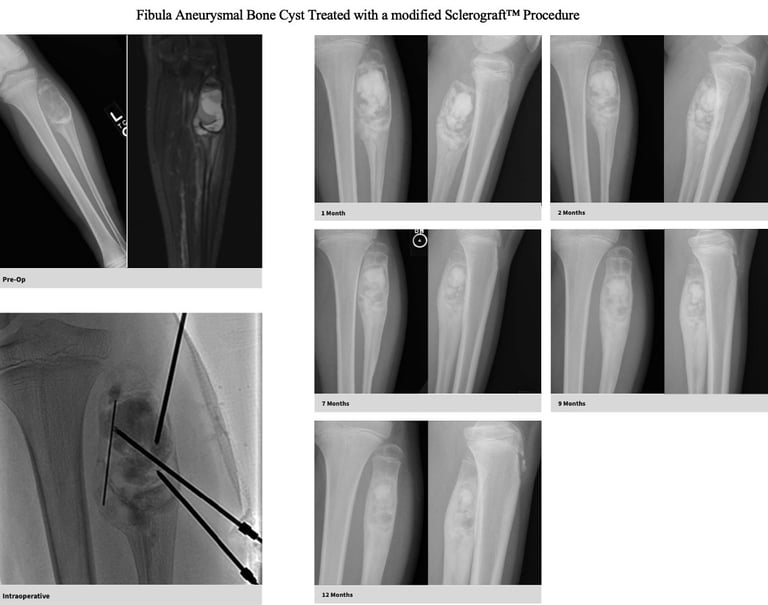

Gallery

Explore our educational resources and images

Utilizing needles, chemical sclerosis destroys the cyst wall and regenerative bone graft is injected via the needles to expedite bone healing.

The doctor uses imaging guidance (like X-ray or ultrasound) to guide needles into the cyst.

Chemical sclerosis using chemicals like doxycycline are washed through the cyst to kill the cyst wall lining

Regenerative bone graft is then injected through the needles and the needles are removed. The bone graft is temporary and is eventually reabsorbed by the body.

Proven success in both UBCs and ABCs